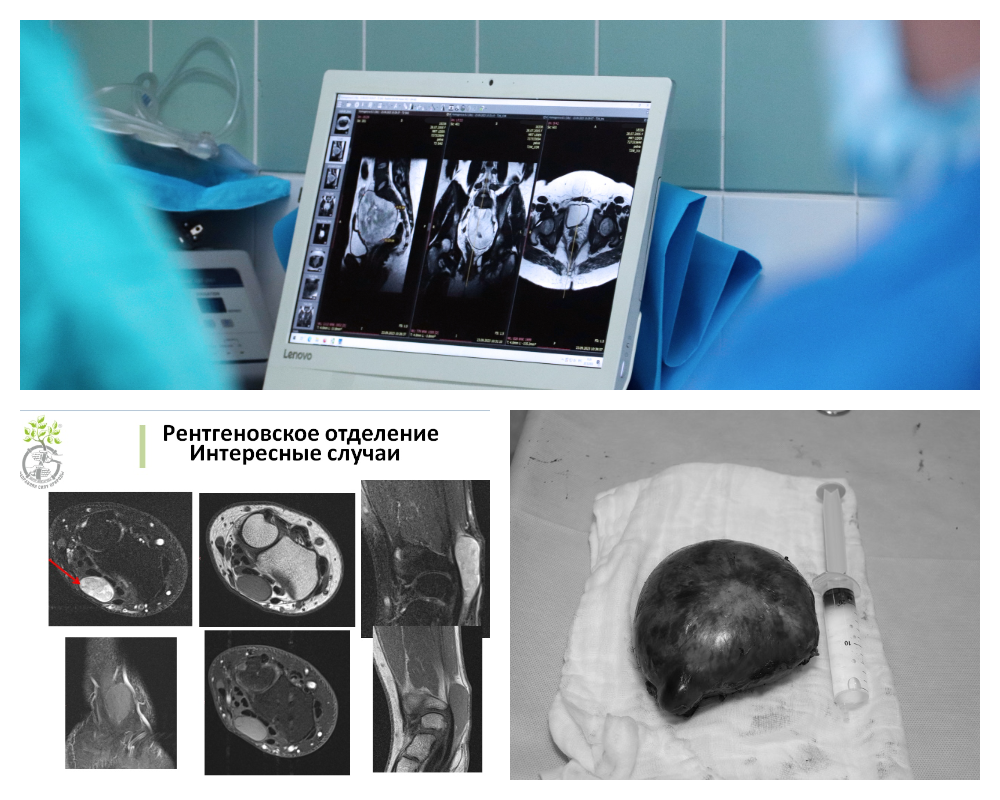

Подобные пациентские истории с диагностикой и лечением шванном и их последствий были в Центре Илизарова в 2023 и 2024 годах. В одном случае новообразование было обнаружено с помощью магнитно-резонансной томографии у пациента в лучезапястном суставе.

Во втором случае нейрохирургами Клиники патологии позвоночника и редких заболеваний и врачами Курганского онкологического диспансера у 18-летней пациентки была удалена гигантская шваннома корешка спинномозгового нерва с прорастанием в область малого таза. Как раз это был тот самый случай неожиданной находки на профосмотре перед устройством на работу.